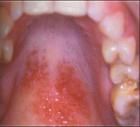

扁平苔藓是一种比较常见的粘膜病,其发病的原因也是比较复杂的。经大量扁平苔藓病历的总结得出,绝大部分的病症的发生与精神情绪存在有一定的关系。

对于患者来说,如有的心情郁闷、气怒、悲伤、焦虑、急躁就比较容易出现扁平苔藓的症状表现。有的患者是工作压力过大,过于紧张和劳累,长期得不到很好的休息,给自身造成了超负荷的作业,因此比较容易造成病症的发生。

而有的患者就是睡眠不好,心情长时间的比较的烦躁。也有的是因为打麻将上火或熬夜,生活无规律,饮食无规律。

因多种原因的共同作用,导致体内出现紊乱、五脏六腑功能失调而发病。也有的患者病症的发生与牙齿长期不良剌激有关。